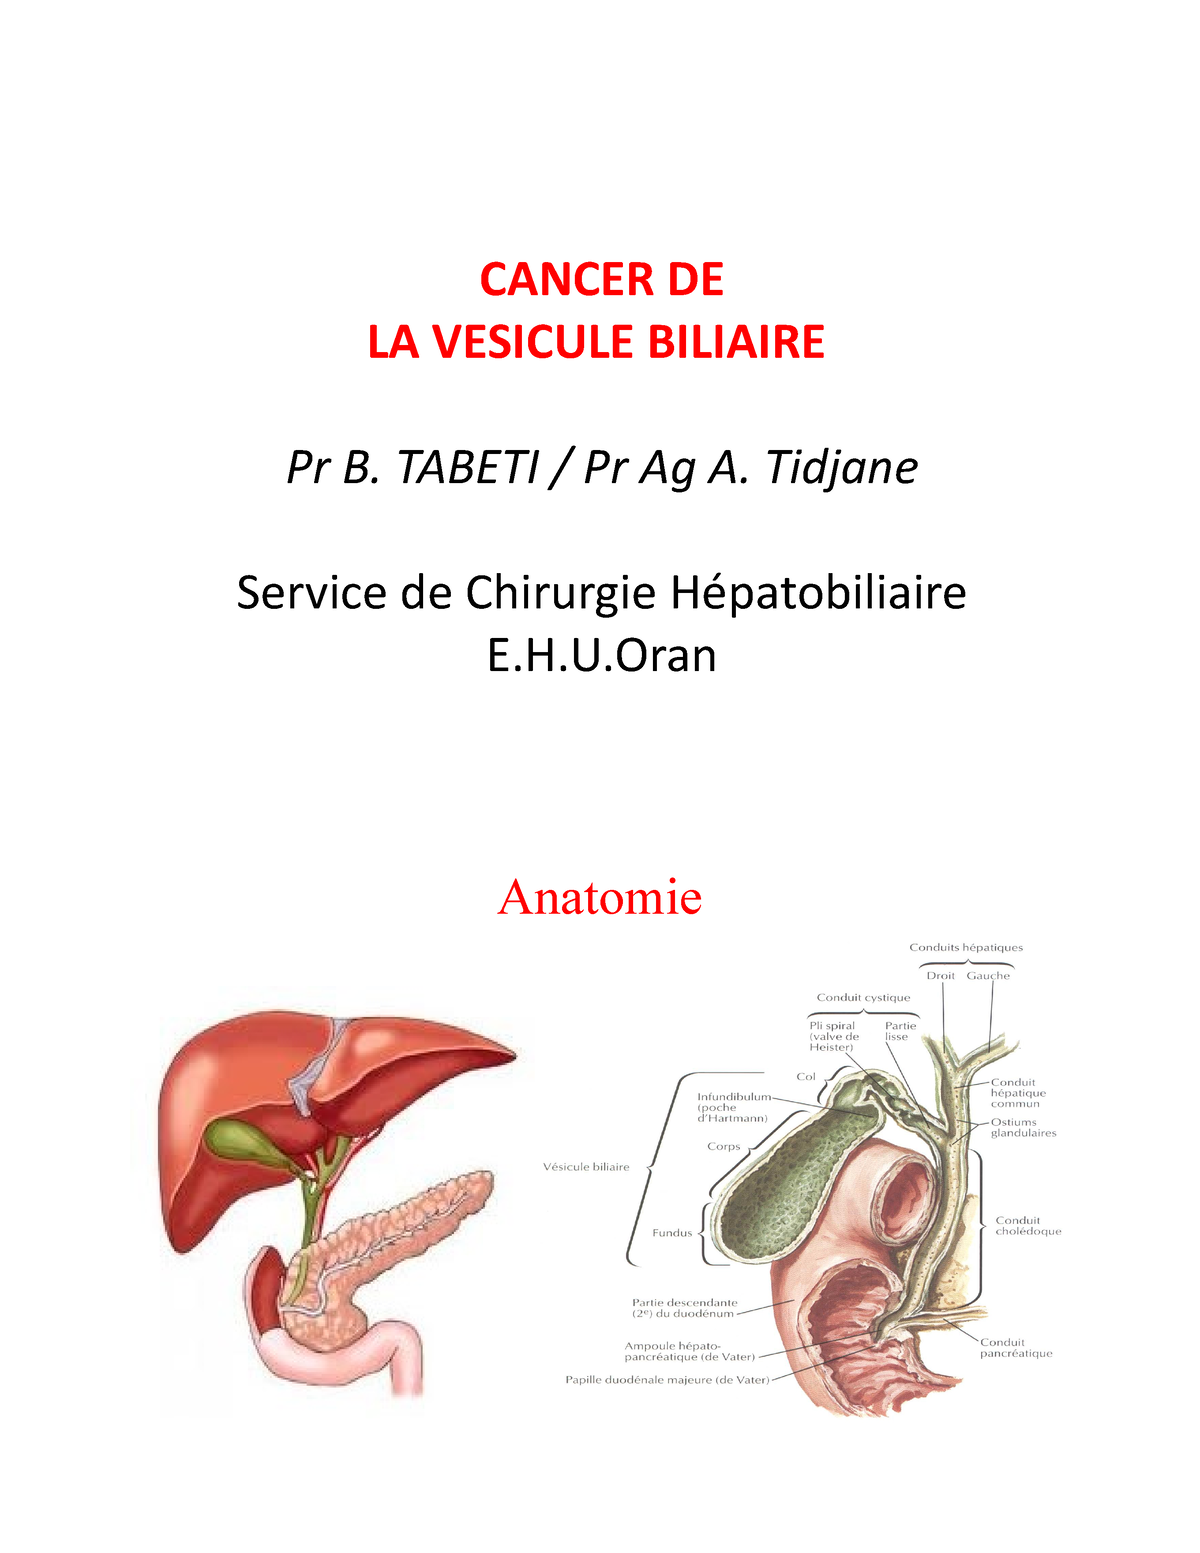

La vésicule biliaire joue un rôle essentiel dans la digestion des graisses. Un dysfonctionnement, causé par une tumeur, perturbe ce processus. Plusieurs symptômes digestifs peuvent alors apparaître.

La bilirubine est un pigment jaune produit lors de la dégradation des globules rouges. Normalement, la vésicule biliaire et le foie contribuent à son élimination. Une obstruction des voies biliaires, causée par une tumeur, empêche cette élimination.